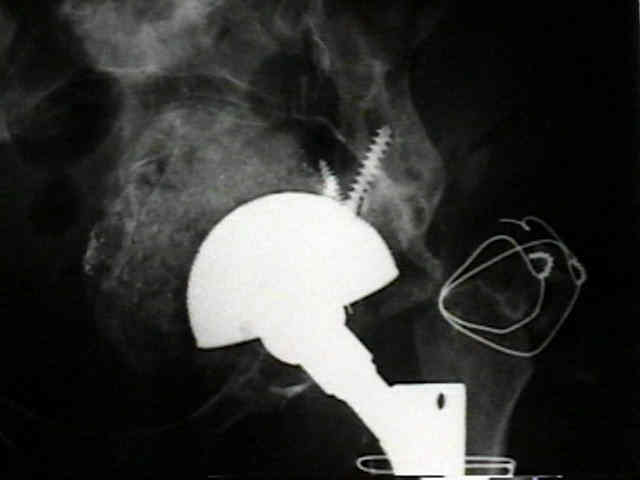

Loosening of Cemented Acetablar Components

(cemented acetabular component)

- radiolucency upto 2 mm wide with or without a surrounding fine line of density may develop in one or more of the the three zones about cement mass in the pelvis;

- as in the femur, radiolucency is produced by the dense fibrous membrane and in some areas, fibrocartilage that forms about the surface of the cement and the surrounding shell of reactive bone;

- loosening commonly occurs at the stem cement interface, but it rarely occurs at the cup cement interface;

risk factors for loosening

- as noted by Kobayashi S, et al (1997), the most important factor for loosening is rapid wear of the polyethylene (more than 0.2 mm per year), followed by atrophic osteoarthritis (DJD w/o osteophytes);

definite loosening

- migration of component of more than 5 mm;

- crack in cement mantle;

probable loosening

- continuous radiolucent line > 1-2 mm wide at the bone cement interface;

- as pointed out by Hodgkins et al 1988, the finding of a continuous radiolucent line about the acetabular component indicates loosening in 94% of patients;